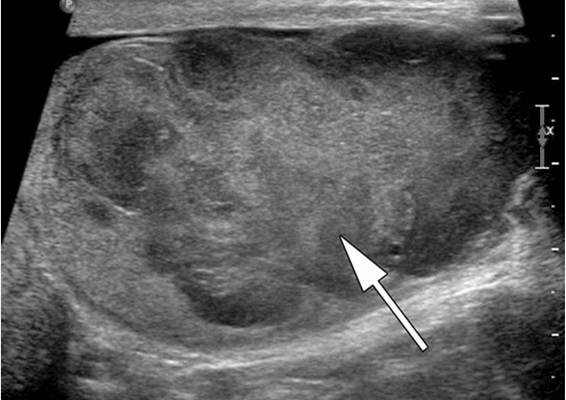

![Тератома яичника (УЗИ)]()

Рисунок 3. – тератома яичника а –УЗИ, б — МРТ.